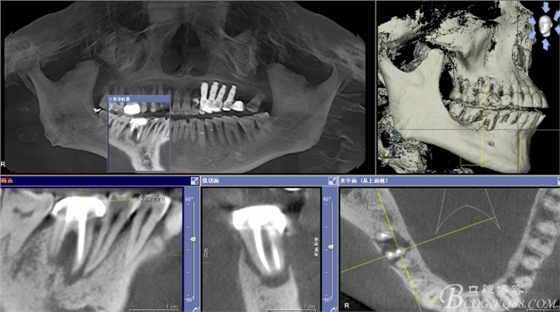

CT可見根管內(nèi)有白色顯影物和根周較大暗影

從根管影像看治療還是不錯的,

懷疑牙根微裂,

所以建議患者手術(shù)探查